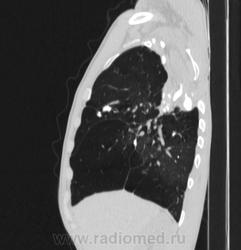

Состояние после торакопластики.

Молодой человек 30 лет, в 04 году выявлен фиброзно-кавернозный ТБ, в течение 12 месяцев лечился в стационаре, прооперирован-5реберная торакопластика справа, через 3 года переведен в 3ГДУ, в 10году снят с ДУ по излечению. Пришел провериться по ухудшению состояния. На КТ легких данных за рецидив ТБ, вроде нет. С " торакопластикой" был единственным пациентом на учете.

Состояние после правосторонней 5-реберной торакопластики по поводу ФКТ.Грубые остаточные изменения:поликистоз,буллезно-дистрофические изменения,плевропневмоцирроз правого легкого..Нет ли  мелкоочаговой диссеминации в обоих легких?Нужен Rархив.(ПТД).

Нет, это кальцинаты и более плотные уже. Архив только пленочный, 8 лет назад "цифры" не было. Можно и пленку перефотать...

Редко встречалось, а на КТ вижу впервые, спасибо за случай! На показанных изображениях отсевов не увидела.